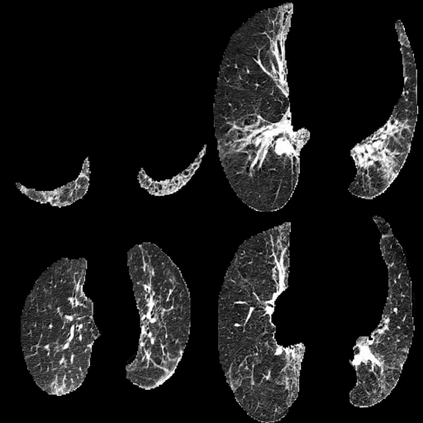

In the field of medical imaging, particularly in tasks related to early disease detection and prognosis, understanding the reasoning behind AI model predictions is imperative for assessing their reliability. Conventional explanation methods encounter challenges in identifying decisive features in medical image classifications, especially when discriminative features are subtle or not immediately evident. To address this limitation, we propose an agent model capable of generating counterfactual images that prompt different decisions when plugged into a black box model. By employing this agent model, we can uncover influential image patterns that impact the black model's final predictions. Through our methodology, we efficiently identify features that influence decisions of the deep black box. We validated our approach in the rigorous domain of medical prognosis tasks, showcasing its efficacy and potential to enhance the reliability of deep learning models in medical image classification compared to existing interpretation methods. The code will be publicly available at https://github.com/ayanglab/DiffExplainer.